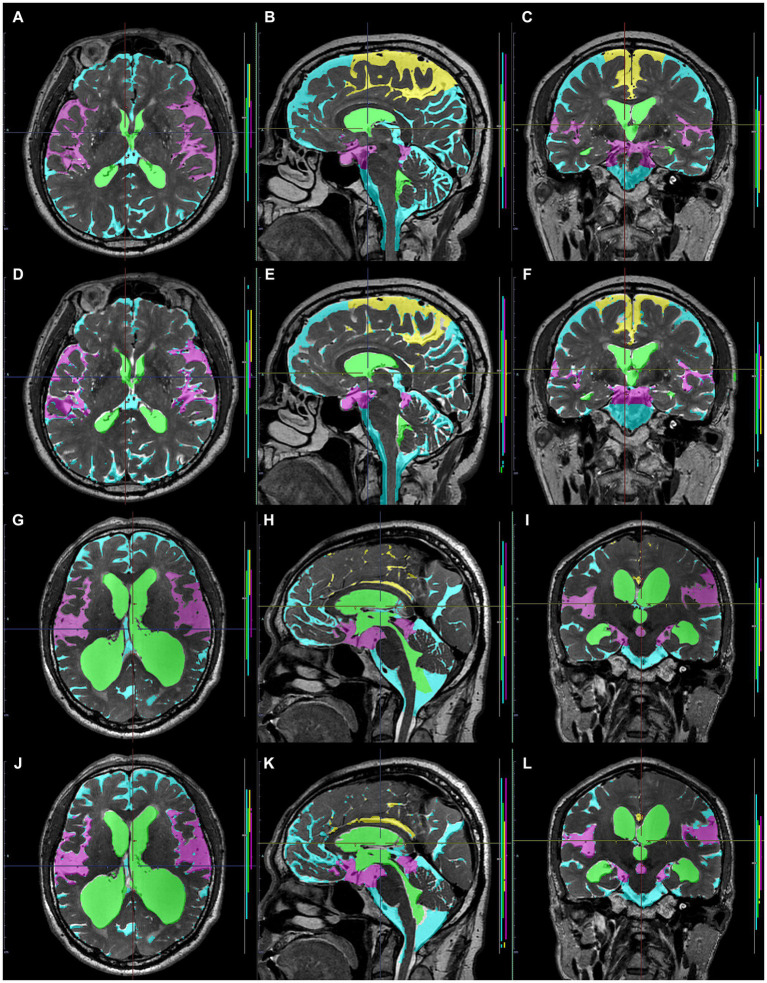

Preparation for data processing of deep learning

As ground truth labels in our AI models, input image masks for volumetric semantic segmentation on the 3D T1-weighted MRI were created by combining manual segmentation with the 3D Viewer and fully automatic segmentation with the Brain Subregion Analysis applications (Figures 1A–C) on an independent 3D volume analyzer workstation (SYNAPSE 3D; FUJIFILM Corporation, Tokyo, Japan). In the Brain Subregion Analysis application, intracranial spaces were segmented fully automatically into 26 subregions including ventricles and SAS within 1 min (ref. Yamada et al., 2023c). The input image masks from 3D T2-weighted MRI were also created using our original method, combining a simple threshold algorithm and manual segmentation (Figures 1D–F), as previously reported (ref. Yamada et al., 2015, ref. 2016a,ref. b). Total SAS were further segmented into the Sylvian fissure and basal cistern, and the high-convexity SAS, which was defined as the location above the body of the lateral ventricles, with the lateral end 3 cm from the midline, the posterior end in the bilateral posterior parts of the callosomarginal sulci, and the anterior end on the coronal plane perpendicular to the AC–PC line passing through the front edge of the genu of the corpus callosum (Figure 2; Supplementary Videos S1–S4) (ref. Yamada et al., 2023a). All input image masks as the ground truth labels were transferred to the SYNAPSE Creative Space for cloud-based AI development service (FUJIFILM Corporation). All masks were processed and formatted into a form that could utilize the training or inference process. Regarding the output of the inference process, feature maps were obtained. Overall, 159 T1-weighted images were assigned to 110 images for training, 30 for internal and 19 for external validation (test), and 180 T2-weighted images were assigned to 130 images for training, 30 for internal validation and 20 for external validation. Inference was performed in the images for internal validation and external validation.

Volumetric semantic segmentation

Training and internal validation of the 3D U-Net model for semantic segmentation were repeated over 1,000 times (Figures 4–7; Supplementary Figures S1, S2). Overall, the intracranial CSF space, total ventricles, total SAS, Sylvian fissure and basal cistern, and the high-convexity SAS were segmented fully automatically from 3D T1-weighted (Figure 8) and T2-weighted MRIs (Figure 9). There was no significant difference between manually and automatically segmented volumes of the total ventricles, total SAS, high-convexity SAS, and Sylvian fissure and basal cistern (Table 3). Among the segmented regions, the mean Dice scores for the total ventricles were highest (0.85 from T1 and 0.83 from T2), those for the Sylvian fissure and basal cistern were second highest (0.70 and 0.69), and those for the high-convexity SAS were lowest (0.68 and 0.60). The mean Dice coefficient scores for all of the regions segmented from the T1-weighted image were superior to those from the T2-weighted image. The mean differences between the manually and automatically segmented volumes of the high-convexity SAS were smaller (T1 and T2; 3.6 mL and 4.2 mL) than those of the Sylvian fissure and basal cistern (5.3 mL and 8.3 mL).